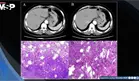

El examen físico reveló ictericia escleral intensa, hepatoesplenomegalia, hematemesis activa abundante y orina color negro característico de fiebre del agua negra. Los estudios paraclínicos demostraron falla renal aguda severa con creatinina 12.8 mg/dL, urea 529 mg/dL y BUN 246.87 mg/dL, elevación marcada de transaminasas (AST 214 U/L, ALT 409 U/L), anemia moderada (hemoglobina 9.8 g/dL), trombocitopenia (61,000/µL) e hiperbilirrubinemia notable. Las serologías para hepatitis B, C y VIH resultaron negativas, y la radiografía de tórax fue normal.

El diagnóstico integrado fue malaria grave por Plasmodium falciparum complicada con malaria cerebral, lesión renal aguda, disfunción hepática, anemia, trombocitopenia y sangrado gastrointestinal. Se inició manejo multidisciplinario inmediato incluyendo artesunato intravenoso cada 24 horas, hemodiálisis de emergencia, nutrición parenteral, antibioticoterapia de amplio espectro y anticonvulsivantes.

La parasitemia de 3.52% en un adulto inmunocompetente sugiere replicación parasitaria masiva con probable secuestro de eritrocitos parasitados en microvasculatura cerebral, generando lesión endotelial de la barrera hematoencefálica, isquemia y edema cerebral.

La fiebre del agua negra, manifestación de hemólisis intravascular masiva evidenciada por orina color té negro, resultó de destrucción eritrocitaria por el parásito y disfunción hepática concomitante. Aunque esta entidad puede asociarse a deficiencia de G6PD y ciertos fármacos, no fue posible confirmar esta asociación por limitaciones en disponibilidad de pruebas diagnósticas.